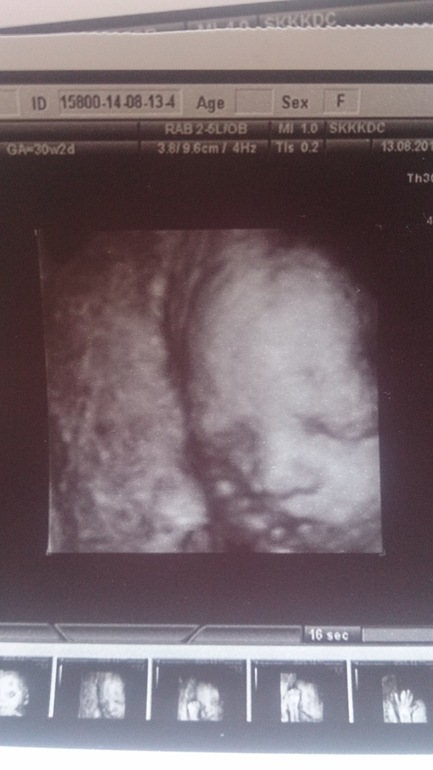

Наше третье плановое 3д узи

Мои неделькиЯ под огромным впечатлением))))) Она такая хорошенькая, наша крошечка)) Муж в ступоре сидел)) Но огорчило то, что доча села на попу и намотала пуповину...((( Страшно, что теперь делать? Узист сказала, что упражнения нежелательно делать, если есть обвитие, что теперь? Кесарево? Весит мы 1650 в 30 недель и 2 дня. А сколько весили ваши малыши на таком сроке и сколько родились?